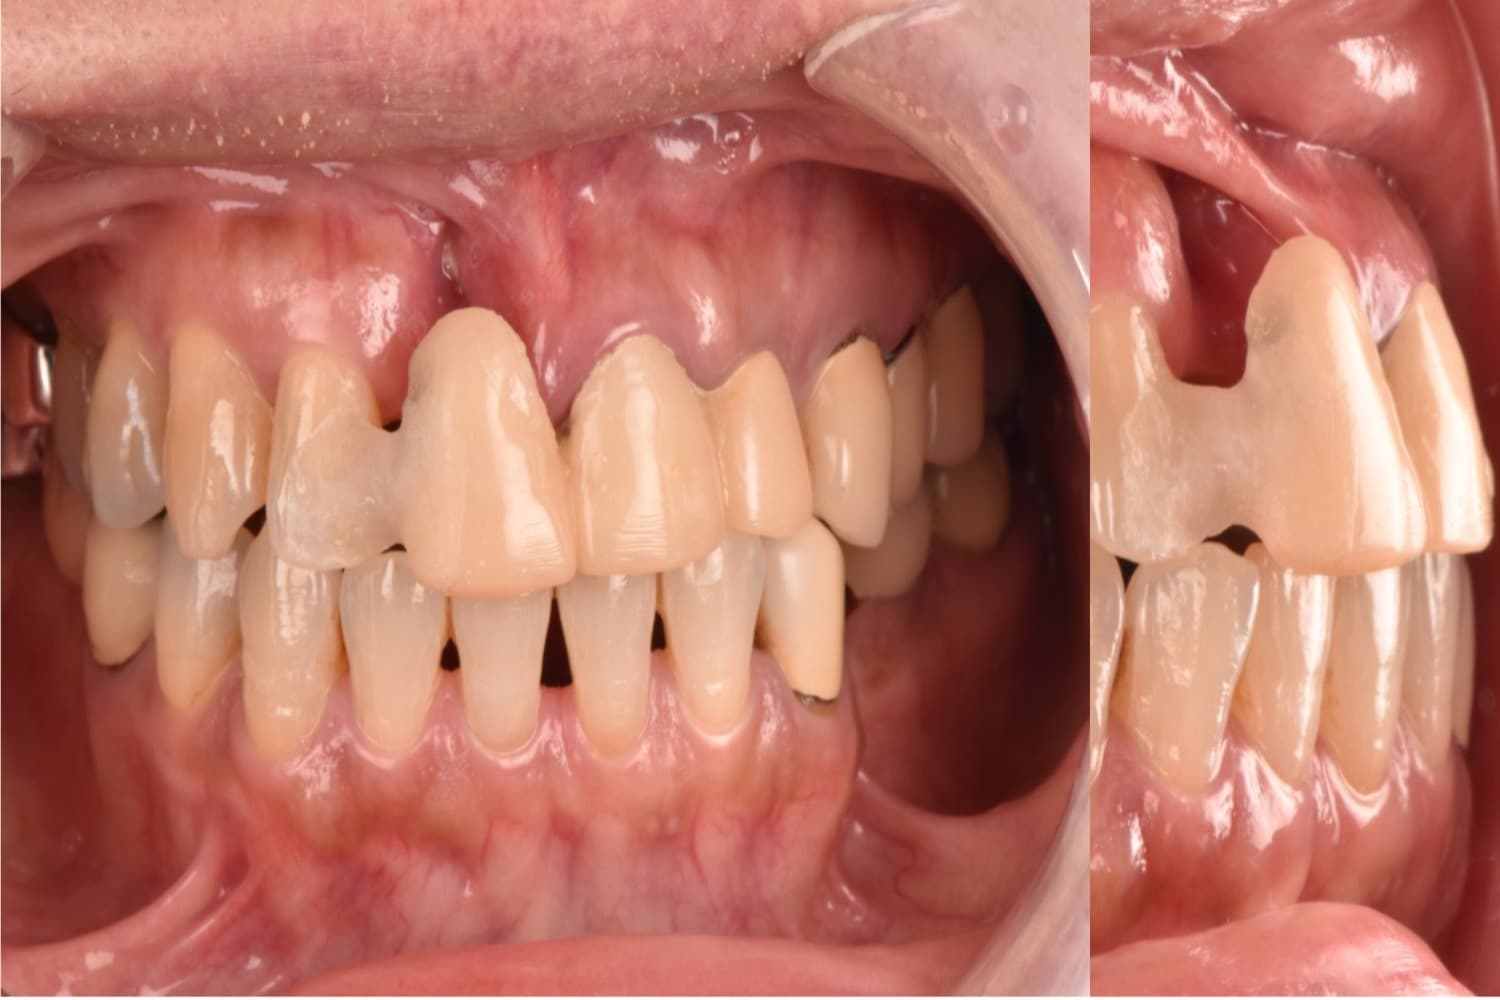

右上1の前歯部のインプラント治療

Before

After

年齢

50代

性別

女性

主訴

前歯を綺麗にしたい

治療期間

10カ月

治療回数

15回

費用

913,000円

副作用・リスク

清掃状態等によりインプラント周囲に炎症を起こす可能性があります。